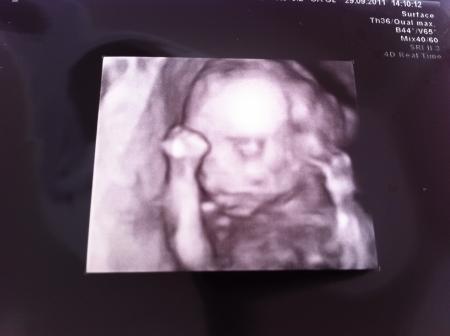

hallo nein, das kam falsch rüber ;-). ich war natürlich regelmäßig beim arzt, nur leider gab es nicht immer us und somit hab ich 10 wo keinen us gehabt. ich hab durch die überweisung nichts bezahlt. war sogar 4d us. häng mal noch ein bildchen mit an :-) lg anja

Bild zu